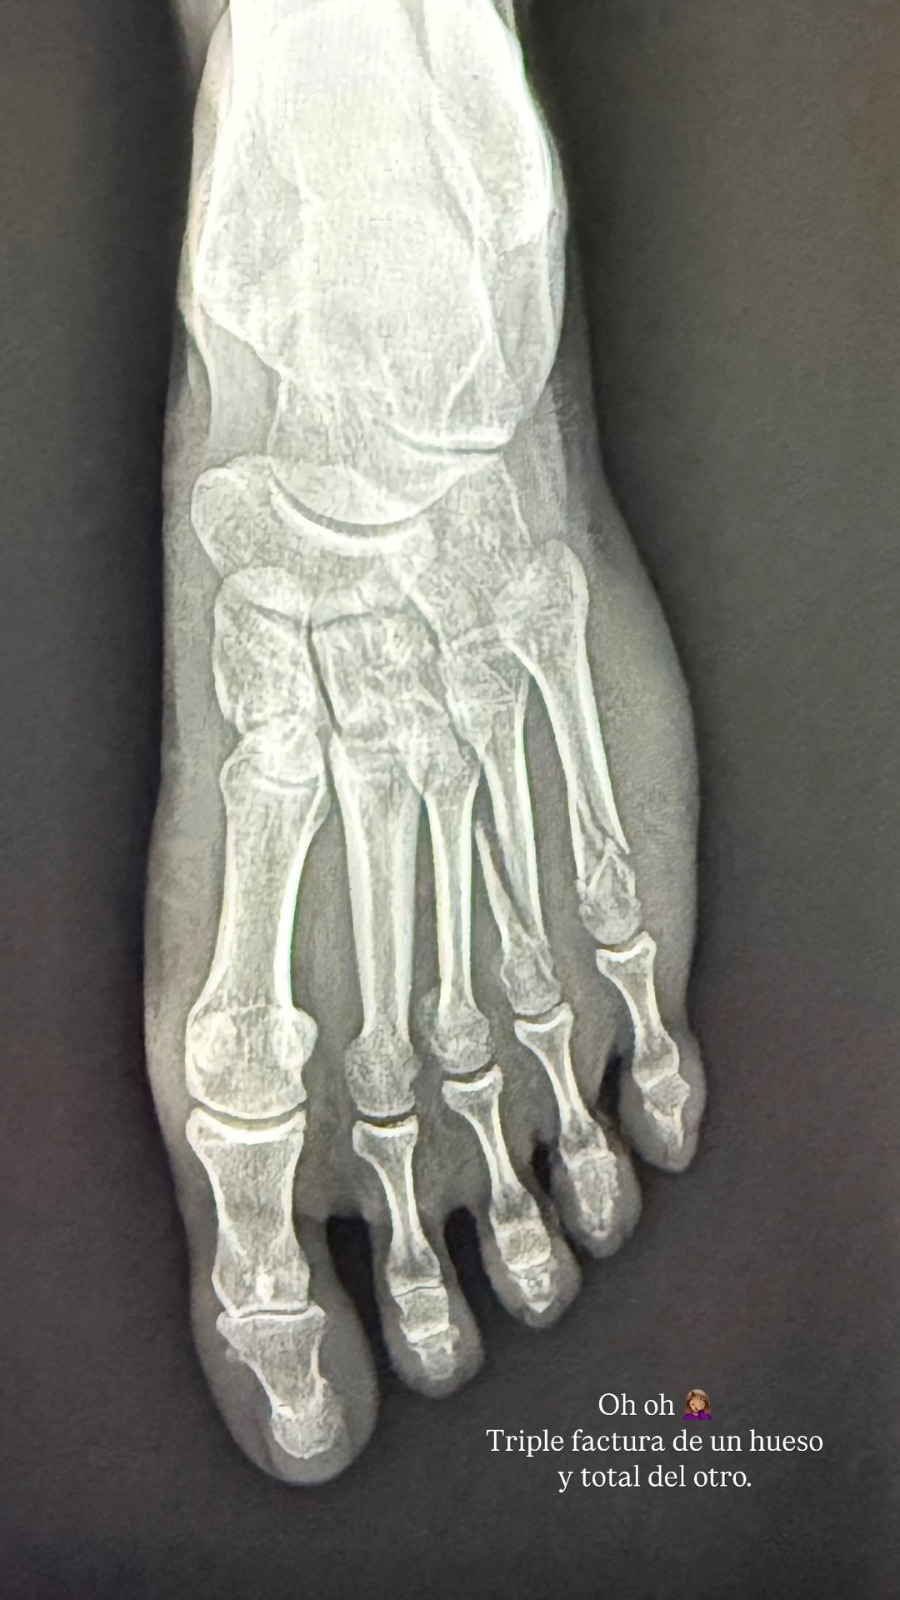

Cuatro horas después, Leonor nuevamente publicó en sus redes sociales una historia en la que aparece una radiografía de su pie, demostrando que el accidente doméstico, que podía parecer una anécdota más, se agravó.

LO ÚLTIMOLo anterior porque, según lo que escribió encima, sufrió nada más ni nada menos que sufrió una "triple fractura de un hueso y total del otro".